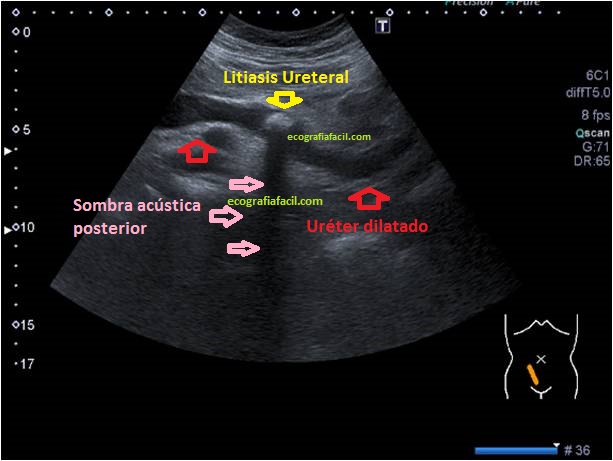

6

El uréter no se ve de manera habitual cuando está sano, en la imagen puedes ver una imagen tubular anecoica con presencia de una imagen hiperecogénica con sombra acústica posterior, que tiene aspecto ecográfico de litiasis y que posiblemente sea el origen de la dilatación. Es decir, el uréter también está dilatado.